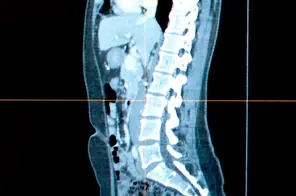

Una nueva herramienta de búsqueda desarrollada por investigadores de Microsoft indexa imágenes médicas del cuerpo humano, en lugar de páginas web. En imágenes de TC, éste encuentra automáticamente órganos y otras estructuras para ayudar a los médicos a navegar y trabajar con imágenes médicas en 3-D.

Los dispositivos de TC utilizan los rayos X para capturar muchas secciones del cuerpo que pueden ser combinadas para crear una representación en 3-D de él. Se trata de una poderosa herramienta para el diagnóstico, pero está lejos de ser fácil de navegar, señala Antonio Criminisi, quien lidera un grupo en Microsoft Research, con sede en Cambridge, Reino Unido, que está tratando de cambiar eso. "Es muy difícil, incluso para alguien muy capacitado, llegar al lugar que tiene que examinar para encontrar el origen de un problema", afirma él.

Cuando se carga una imagen al software de Criminisi, el programa indexa los datos y enumera los órganos que ha encontrado en el lateral de la pantalla, creando una tabla de hipervínculos para el cuerpo. Un usuario puede hacer clic en, por ejemplo, la palabra "corazón" y se le presentará con una vista clara del órgano sin tener que navegar a través de las imágenes manualmente.

Una vez que un se ha encontrado un órgano de interés, al usuario se le muestran dos vistas, una 2-D y una 3-D mejorada, de las estructuras en la zona, y éste puede navegar por la zona tocando la pantalla en la que se muestran las imágenes. La nueva imagen también puede ser automáticamente y perfectamente comparada con otra anterior del mismo paciente, por lo que es fácil ver cómo una enfermedad ha progresado o retrocedido.